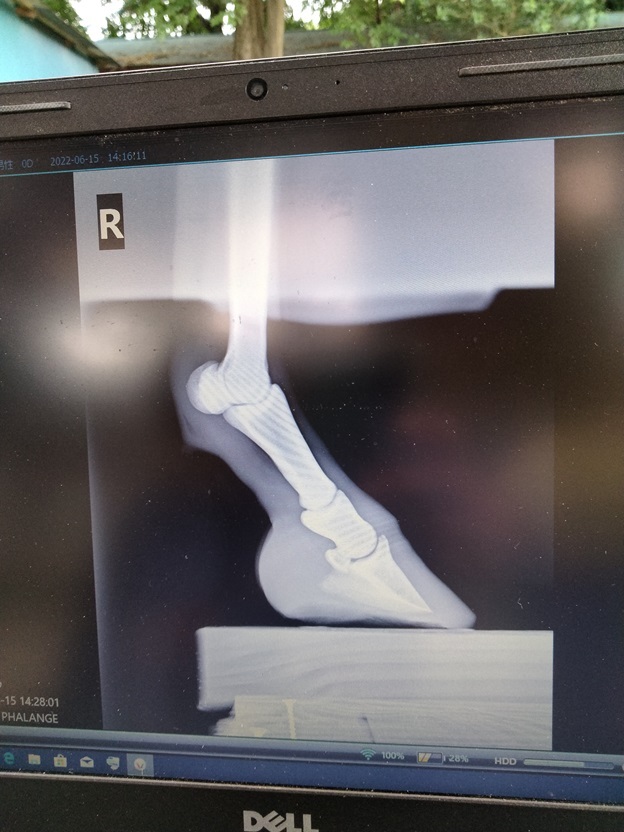

蹄葉炎を否定するため、

すぐに獣医さんにレントゲンを撮っていただきました。

この日は装蹄師さんも同席してくださっていて

獣医さんと装蹄師さんと私とで、

あれやこれやとディスカッションすることができました。

ありがたかったです(´;ω;`)

診断の結果、

初期の蹄葉炎でした。